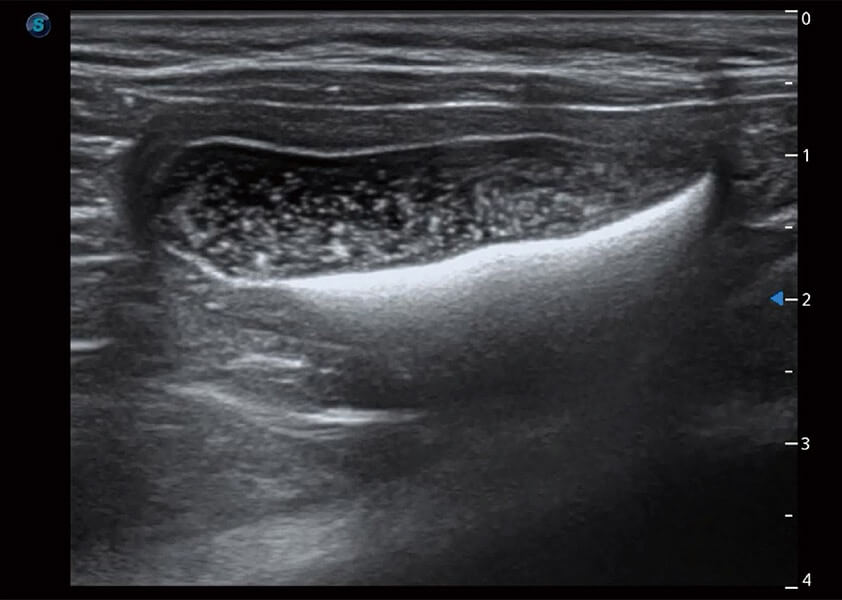

ProPet 60 作為一款高端臺式動物超聲設(shè)備,為動物醫(yī)生的日常診斷提供了一系列貼合動物臨床需求、解決臨床實際問題的高級成像功能。憑借全系列高清探頭,滿足醫(yī)生對腹部、心臟、生殖、淺表、肌骨等成像的所有需求,切實幫助您提升檢查效率,提高診斷信心。